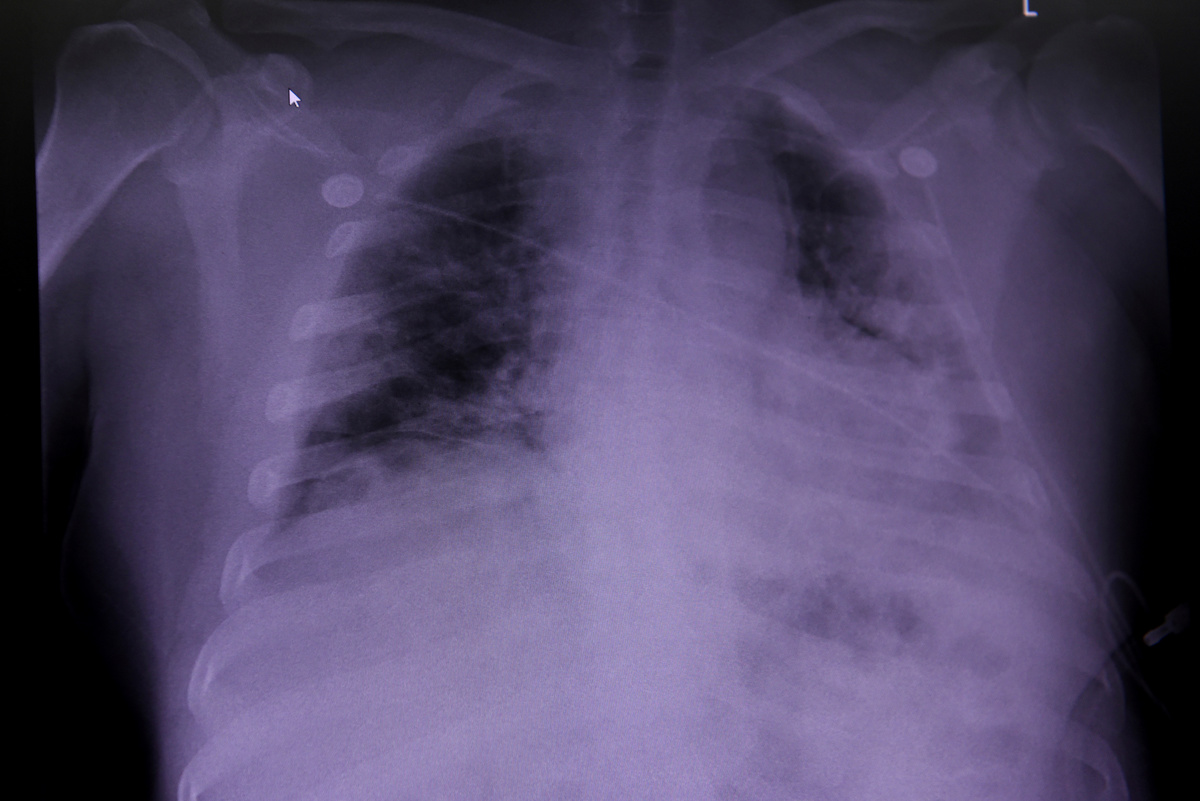

In a telephone interview, Giacca said that, while his research team found no overt signs of viral infection or prolonged inflammation in other organs, they discovered "really vast destruction of the architecture of the lungs", with healthy tissue "almost completely substituted by scar tissue".

One was that patients had extensive blood clotting of the lung arteries and veins. Another was that some lung cells were abnormally large and had many nuclei - a result of the fusion of different cells into single large cells in a process known as syncytia.